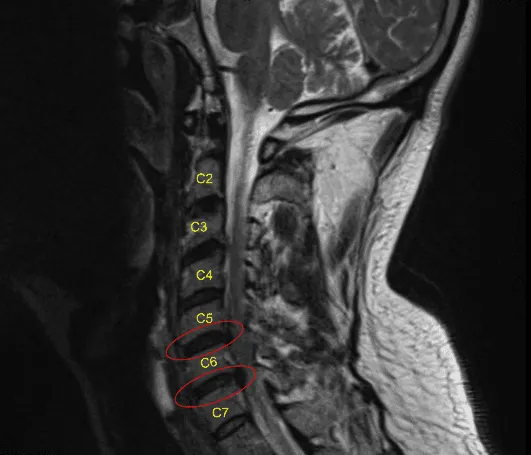

La paciente es una mujer de 40 años que fue atendida en la consulta con quejas de dolor que irradiaba a ambas extremidades superiores, con debilidad, hormigueo y entumecimiento. Sus hallazgos de examen físico e imagen fueron consistentes con estenosis del canal cervical. Había probado un tratamiento no quirúrgico que no ha funcionado. Hablamos sobre las opciones de tratamiento y acordamos el manejo quirúrgico. Se obtuvo el consentimiento informado.

Se realizó una disección adicional tanto distal como proximal para abrir la zona. Se utilizó una aguja en el espacio del disco para confirmar el nivel y se encontró que era C5-C6 y se guardó. El disco estaba marcado y el disco distal también marcado en C6-C7. El longus colis se elevaba a ambos lados de C5, C6 y C7 para exponer tanto el cuerpo como el disco.

Se usaron separadores Skyline. El pasador de Caspar se pasó a C7 y C6 para distraer a C6-C7. La discectomía de C6-C7 se realizó usando curette y Kerrison. Se realizó una foraminotomía exhaustiva de la C7 bilateral con el uso de los punzones Kerrison número 1 y 2.

Se retiró el soporte del disco. Ahora, el pasador Caspar C7 fue retirado e insertado en C5. La distracción de C5-C6 se realizó utilizando el distractor de Caspar. La discectomía se realizó usando curette y Kerrison #1 mm y 2 mm. Se extirpó la LLP y se extirparon los osteófitos. Se realizó una foraminotomía exhaustiva de la C6 bilateral con el uso de los puñetazos Kerrison número 1 y 2.